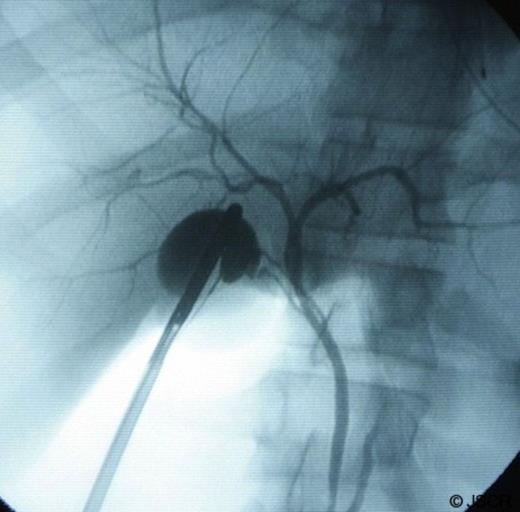

A 21 year old male otherwise healthy with no previous surgical history, presented to the emergency room with the chief complaint of several hours of right upper quadrant pain that started after a large meal. The pain was associated with nausea and non bilious vomiting. The patient described a history of several weeks of right upper quadrant pain after meals but normally it would subside without any intervention. On admission, the patient had normal and stable vital signs and on physical exam there was tenderness to palpation on the right upper quadrant but no peritoneal signs. His laboratory exams were unremarkable with a normal white blood cell count and normal liver function test. A right upper quadrant sonogram showed evidence of cholelithiasis and a questionable double gallbladder. The patient was admitted to the hospital and he was taken to the operating room where he underwent a laparoscopic cholecystectomy using the standard 4 port technique with intraoperative cholangiogram (Fig 1).

Intraoperative cholangiogram showing 2 cystic ducts. Also appreciated in the image: the common bile duct, the common hepatic duct and the left and right hepatic ducts.

During the operation a double gallbladder was found with two separate cystic ducts and two cystic arteries. (Fig 2–3) The intraoperative cholangiogram helped to identify each cystic duct and the operation was otherwise uneventful. The patient was transferred to the recovery room and then to the regular ward. He was started on clear liquid diet postoperatively and he was discharged home on postoperative day one. The pathology report showed evidence of cholelithiasis and chronic cholecystitis.

To aid in the diagnosis the surgeon can use ultrasound, MRCP, ERCP and ultrasound. None of these tools are 100% sensitive and only in little more than 50% of the cases the diagnosis is made preoperatively.(2,3) In our case the ultrasound was questionable but certainly prompted the use of intraoperative cholangiogram to help define the anatomy. In figure 2 two cystic ducts can clearly be seen which makes our case a true gallbladder duplication treated successfully with standard laparoscopic technique.